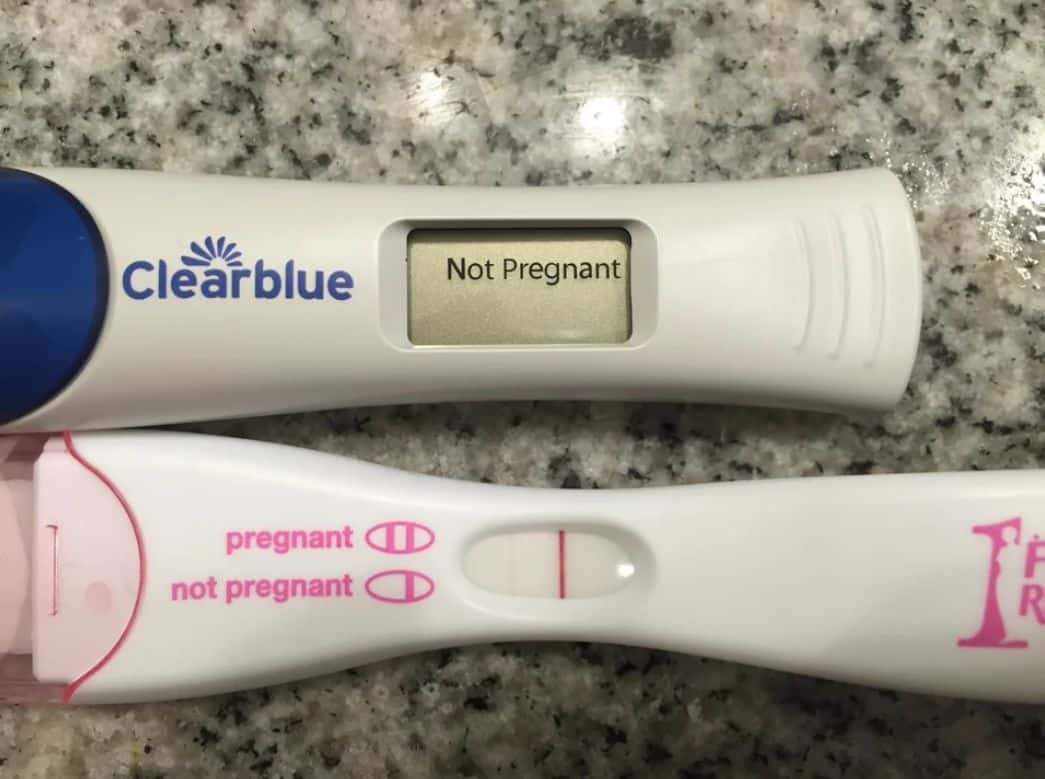

To solve the mystery, this woman had the children take a DNA test.

But Allen’s case was even rarer than that might suggest as this happened as a result of an incredibly uncommon phenomenon known as superfetation.

This is a term given for when a woman is pregnant with two babies who aren’t twins at the same time and according to their chief medical contributor — Dr. Jennifer Ashton — there still isn’t a solid hormonal or physiological explanation for why it happens.

A reproductive medicine specialist named Karen Boyle also said that there were only 10 previously reported cases of superfetation ever occurring.